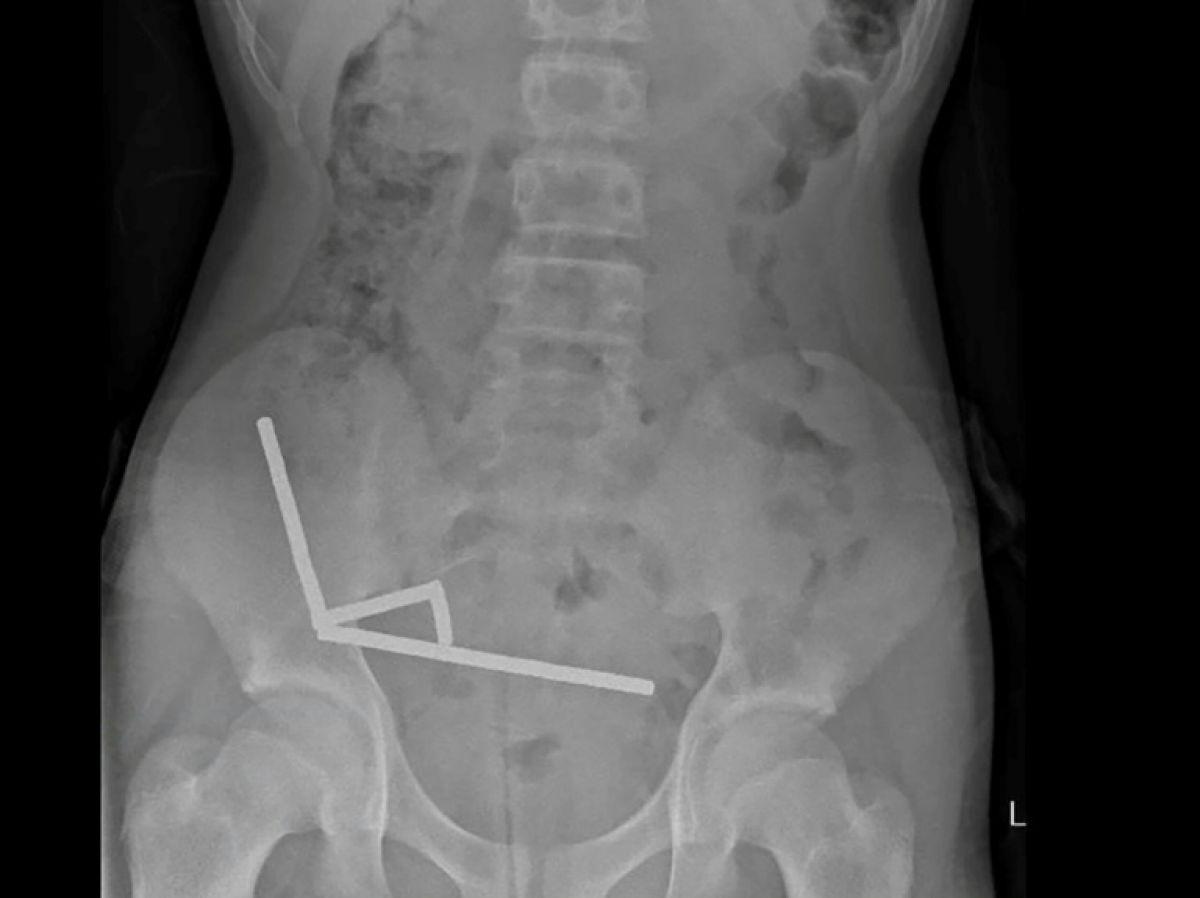

Africa-Press – Togo. Après avoir souffert de douleurs abdominales pendant quatre jours, l’adolescent a été transporté à l’hôpital de Tauranga, sur l’île du Nord. « Il a avoué avoir ingéré entre 80 et 100 aimants puissants au néodyme, de 5x2mm environ, une semaine plus tôt », indique un rapport des médecins de l’hôpital de cet hôpital, publié dans le New Zealand Medical Journal (NZMJ).

Ce type d’aimants, interdit en Nouvelle-Zélande depuis janvier 2013, aurait été acheté sur la plateforme chinoise d’e-commerce Temu. Les médecins ont déclaré que la pression exercée par les aimants avait provoqué une nécrose dans quatre zones de l’intestin grêle et du gros intestin du garçon.

Il a été opéré afin que l’on lui retire les aimants et les tissus nécrosés, et il a pu rentrer chez lui après huit jours à l’hôpital. L’article explique qu’une intervention chirurgicale à la suite de l’ingestion d’aimants peut entraîner des complications, telles qu’une obstruction intestinale, une hernie abdominale et des douleurs chroniques.